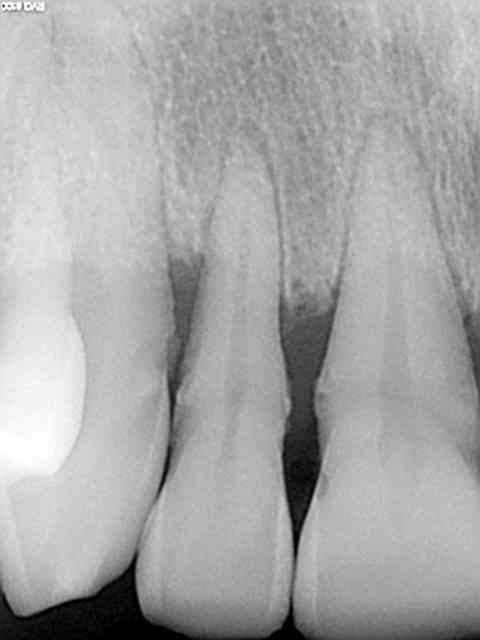

Tu as raison les panos c'est de la merde, mieux vaut faire des status rétroalvéolaires, z56, c'est plus précis. Et puis c'est pas de la médecine hein ? c'est que des chicots pas besoin d'examens complémentaires au pire c'est un quart d'une machoire qui se fait bouffer par un kyste. Je n'avais pas vu ce patient depuis 4 ans , pèche sur 12 asymptomatique. T'en penses quoi ? On attend que ca pète ? Et puis oui, tiens je vais pas faire en plus du chiffre en virant cette dent + curetage péri apical costaud pour la somme astronomique de 33,74 euros mon z56 me suffit,. En plus,si ca se trouve quand ca va arriver je serais en vacances.)))))))